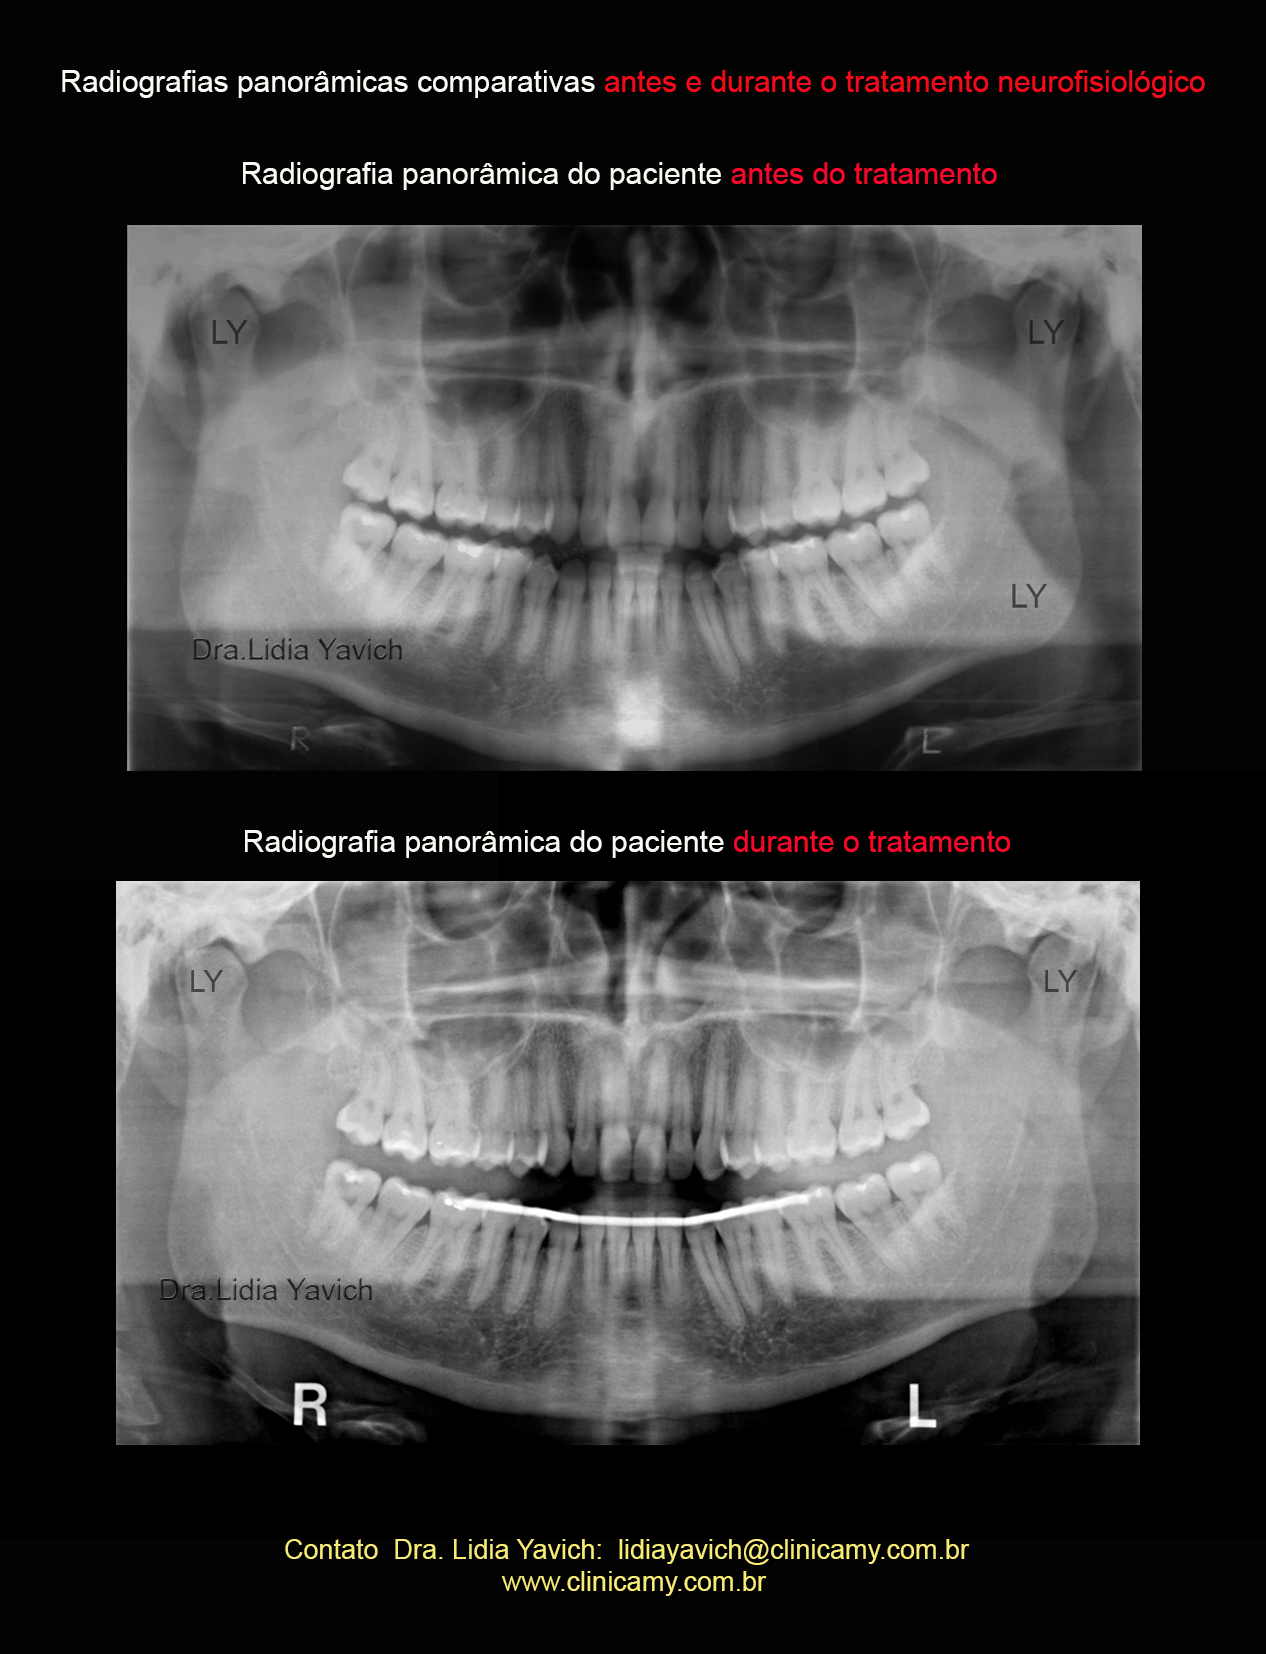

Radiografia panorâmica do paciente antes do tratamento.

Radiografias panorâmicas comparativas: antes do tratamento e durante o tratamento neuromuscular fisiológico.